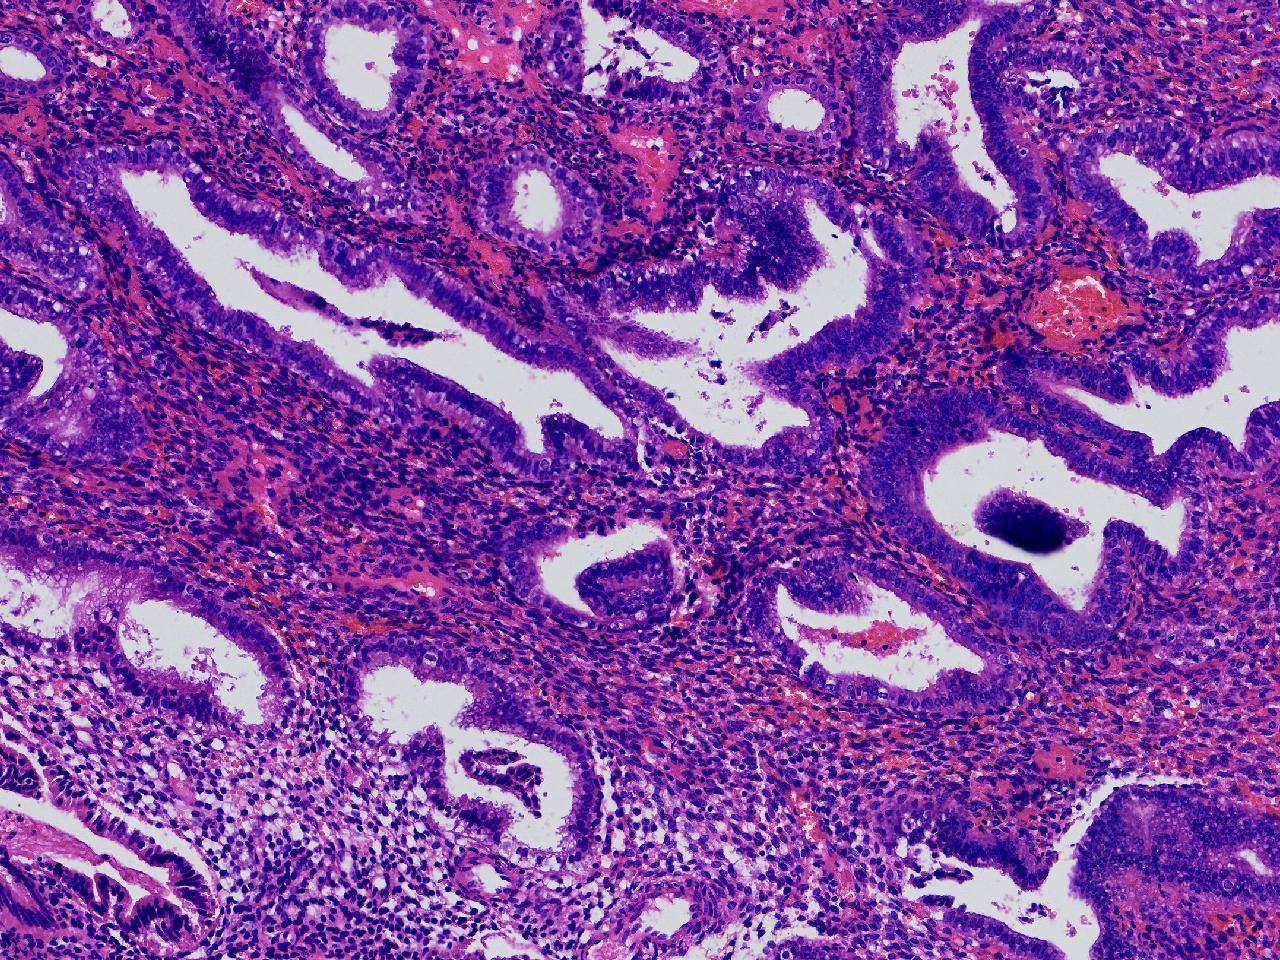

请教。1.有没有非典? 2.内膜是什么变化?

女,50岁,彩超示:粘膜厚度1.1cm。宫腔可见数个高回声,提示宫腔息肉。

子宫内膜+内膜息肉

灰粉色不整形软组织多块,3X3X2厘米。

子宫内膜息肉。

没有非典。

无非典型性子宫内膜增生,子宫内膜息肉

无非典内膜伴息肉。